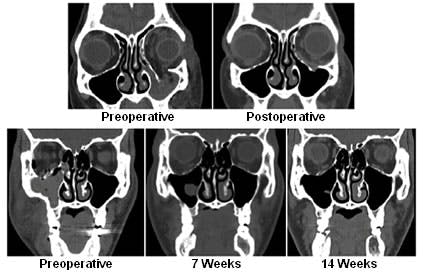

FIGURE 2: Preoperative and postoperative computed tomography scans.